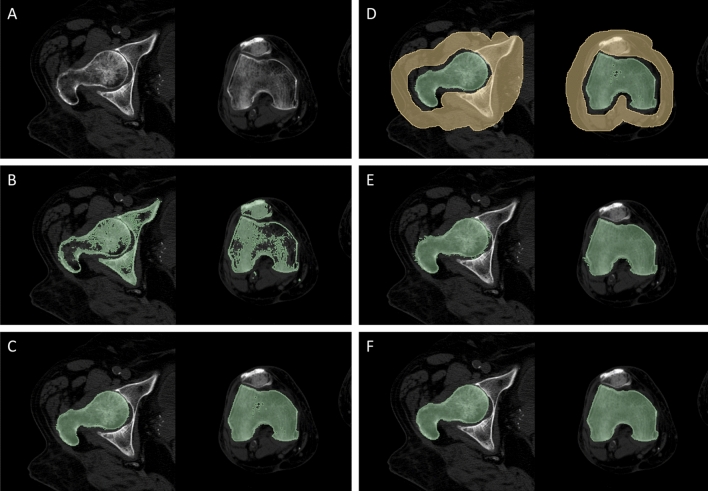

The manual segmentation procedure was implemented in 3D Slicer (version 5.0.3) and it is presented in its main steps in Fig. 5. It started from a thresholding step, where a mask was created by setting a threshold dependent on each patient’s CT scan parameters to isolate only the HU values corresponding to the femur bone tissue (Fig. 5B). Further refinement through manual intervention, especially in complex areas like the hip joint space region, was crucial due to the variations in bone density and overlapping structures. This involved slice-by-slice evaluation by the operator to distinguish the femur head from the iliac bone and the condyles from the patella (Fig. 5C). Subsequently, another mask was created by selecting the other tissues surrounding the femur, such as muscles, tibia or pelvis, with special attention paid to the hip joint space (Fig. 5D). Following this, region growing was carried out thanks to the GrowCut algorithm implemented in 3D Slicer31, which allowed to finalise the femur bone segmentation (Fig. 5E). Eventually, a last manual refinement step was performed, followed by smoothing using a median filter (kernel size of 2 mm) (Fig. 5F). On average, the implementation of the whole manual procedure required 60 min to be run.

Figure 5.

Manual segmentation process. (A) starting CT image; (B) a HU-based threshold-is applied to the CT slices, resulting in the depicted mask (green); (C) the femur bone mask after manual intervention aimed to remove the other bones (e.g., pelvis, patella) from the mask; (D) the creation of a surrounding tissue mask (yellow) comprising what it is not the femur bone of interest, needed to initialise the GrowCut algorithm; (E) the result of the GrowCut-based region growing procedure; (F) the final segmentation mask after manual refinement and smoothing.